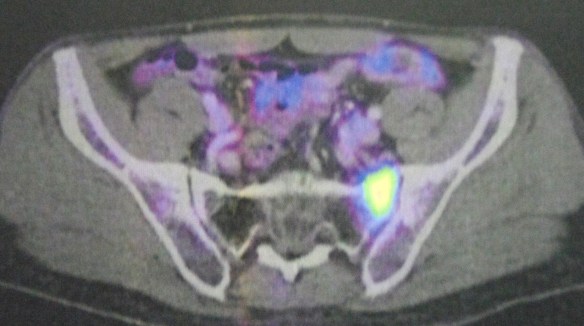

A PET scan on 26 July 2022 showed a 2.1 cm metabolic active lesion seen in the lobe of right lung (see image above). This showed the tumour did not go away! Aman was told to do another biopsy to reconfirm that this mass is still a cancer! However, the oncologist told Aman that there would be NO more chemo or immunotherapy for him. The only option left is surgery.